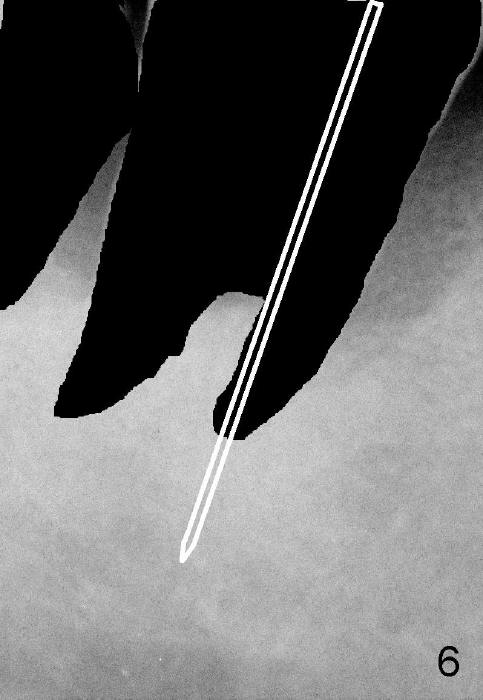

In brief, a large implant is to be placed in the mesial socket of #31. In order to increase primary stability and save autogenous bone (septal bone (Fig.5 S, drawing from Fig.4 after extraction), a pilot drill is used to start osteotomy in the mesial socket (Fig.6 white lines), followed by insertion of osteotomes (Fig.7 white lines, combined with drills). The latter are mainly used to push the septum distally (red arrow). By the time a large implant is placed (Fig.8 green lines), the septum is further pushed distally (red arrow). The remaining distal socket is then filled with bone graft (red circles). How does the surgery end up with?